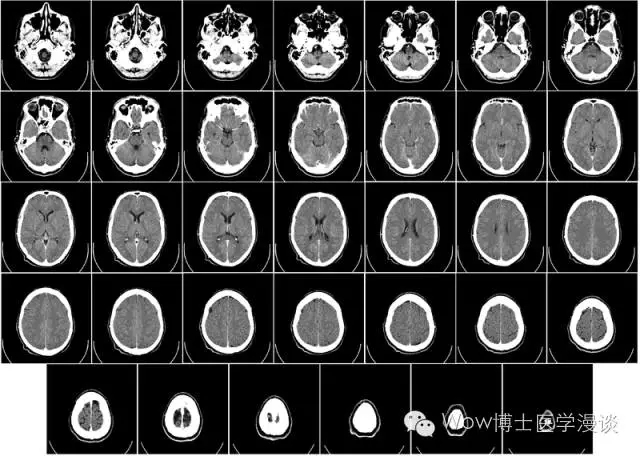

头颅的CT断层扫描图像

而CT(Computed Tomography),即电子计算机断层扫描,它是利用精确准直的X线束对人体进行一个断面接一个断面的扫描,最后可以构建完整人体内部三维图像的方法。CT技术具有扫描速度快,图像清晰等特点,可以精确定位特定的区域。